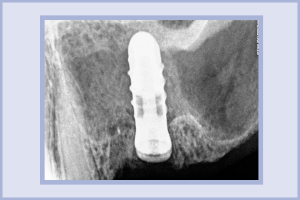

In data 16 ottobre 2009 inserii nel sito edentulo un impianto Leone diametro 4,8 per 10 mm di lunghezza, associato ad un intervento di rialzo del seno per via transettale, senza l’apporto di alcun riempitivo (Fig. 7). In data 29 ottobre 2009 tolsi i punti di sutura e dimisi il paziente che non presentava alcuna sintomatologia, né problema (Fig. 8).

- Fig. 7 – RX di controllo post-operatorio

Nei mesi di aprile e maggio 2010 protesizzai l’elemento. Il 20 ottobre 2013 la situazione radiologica era la seguente:

La piramide ossea intorno all’impianto mostra un guadagno di struttura, quantificabile con un calcolo approssimativo con il programma KODAK Dental Imaging Software 6.8 di oltre 5 mm.